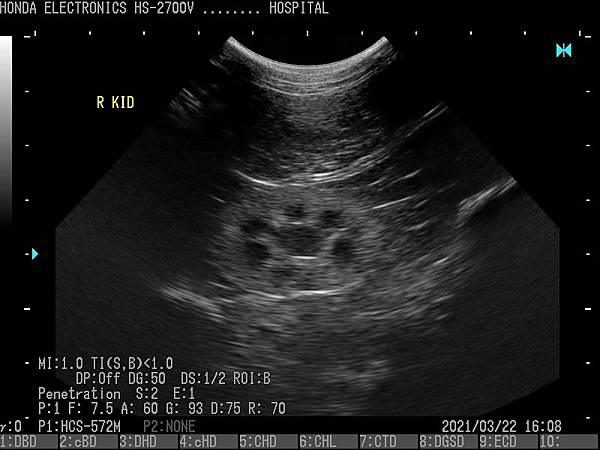

- 通過H-res獲得清晰豐富的單色圖像

HONDA獨創的圖像增強技術 H-res(我們的分辨率技術)

多年來超聲波技術的發展,結晶為“ H-res”圖像增強技術。

可以通過針對每種應用和探頭調整“ H-res”參數來獲得最佳圖像。

* 分辨率可在較淺的區域可視化精細的組織結構。* 穿透力可以在更深的器官中顯現出良好的分辨率。* 邊界可視化骨骼以進行觀察。* 清晰度降低了血管中的噪音。* 溫和會降低圖像增強效果。* OFF具有直接的超聲圖像。